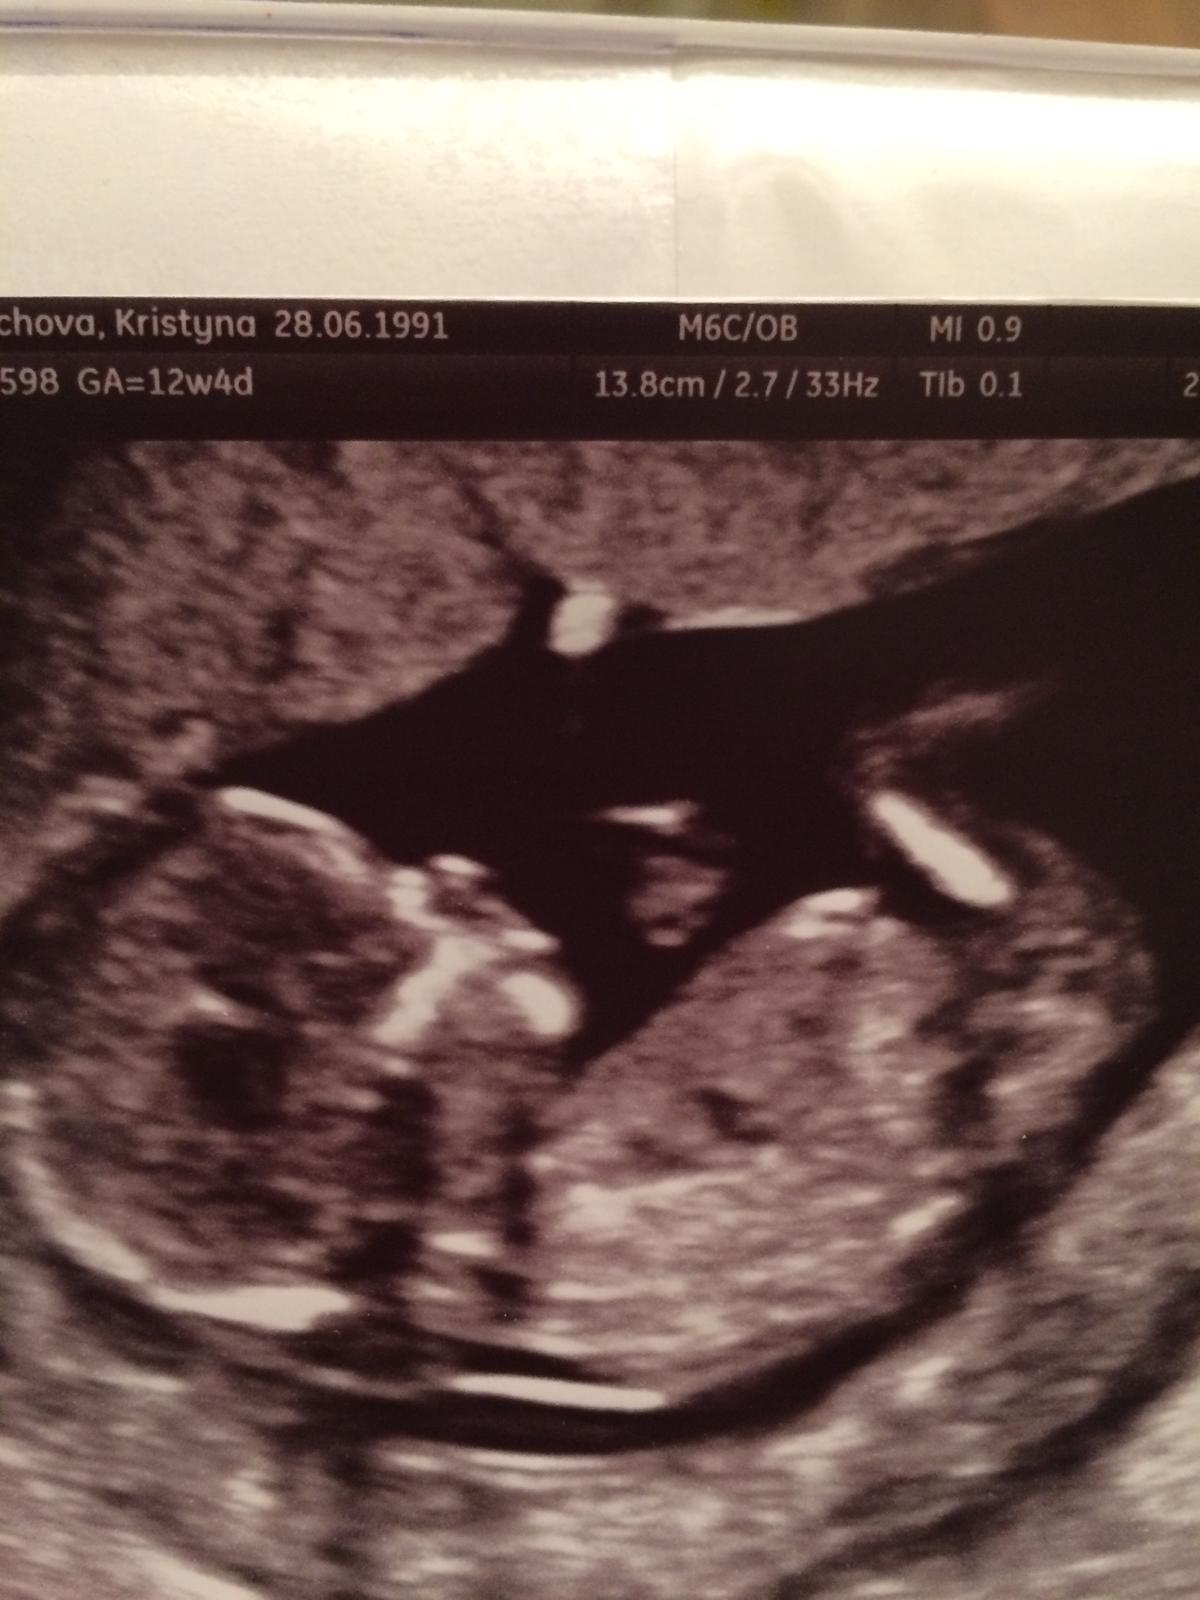

Je to holčička nebo chlapeček? Foto ultrazvuku

Holky, jak v těch flecích dokážete rozeznat kluka od holky? Já tam nepoznám nic, proto ani nemůžeme nic odhadovat...

@puutalo ve kterych flecich ?? 😀

@puutalo toto je pika a okolo nozicky 😉

@mariejosef Chápu to správně, že to je foceno jakoby zespod?

@puutalo ano roztahla nozky a blik ale oblicej ukazat nechtela 😝

Tak tohle už snad nemůže být jasnější 😀 Kluk jako vyšitý 👍

@janyshka u @mariejosef je to teda holccicka jak vysita. po dvou klucich jsem mela uplne stejny UTZ a ted uz s braskama spi doma skoro rocni slecna 🙂

@mariejosef myslím ten první obrázek, který zahájil diskuzi. ...